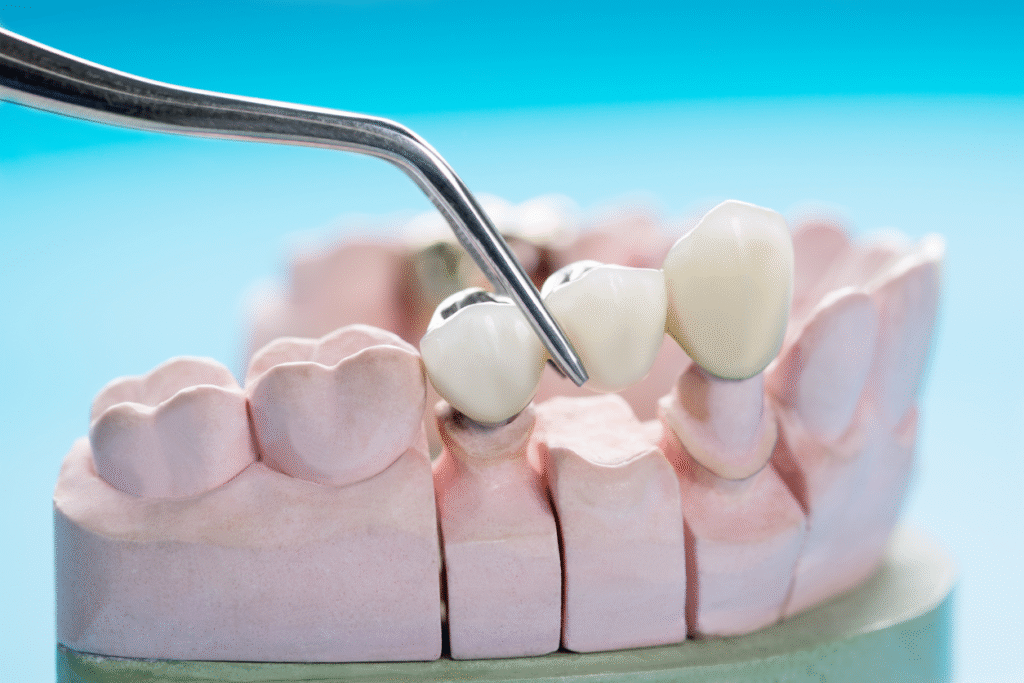

1. Dental Bridge

A Dental bridge in Bangalore is a restoration that bridges the gap left by a missing tooth. It typically uses crowns on the neighboring teeth (the abutments) and a false tooth (pontic) between them. It’s fixed in place and does not come out.

This is one of the most popular missing tooth replacement options.